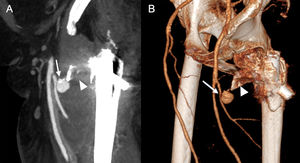

29-year-old man on peritoneal dialysis with a history of renal transplant who had embolization of the transplanted kidney one month ago, and since then developed a mass in the right inguinal region where the puncture was made. Sagittal maximum intensity projection (A) and 3D (B) CT angiography reconstructions of the right lower limb in arterial phase showing a bilobed pseudoaneurysm (arrow) arising from the right common femoral artery.